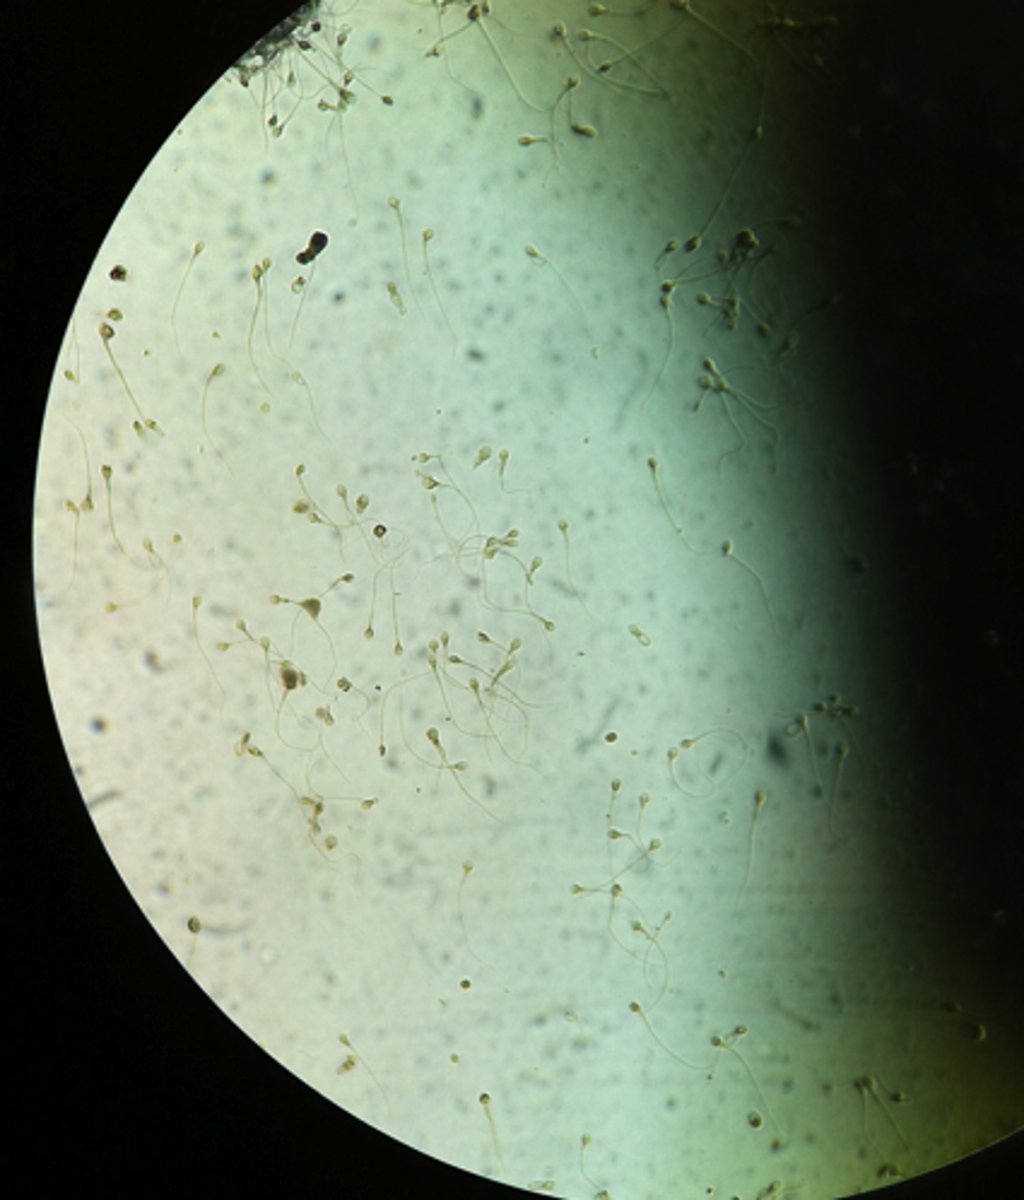

Sperm

Spermatogenesis in Seminiferous Tubules